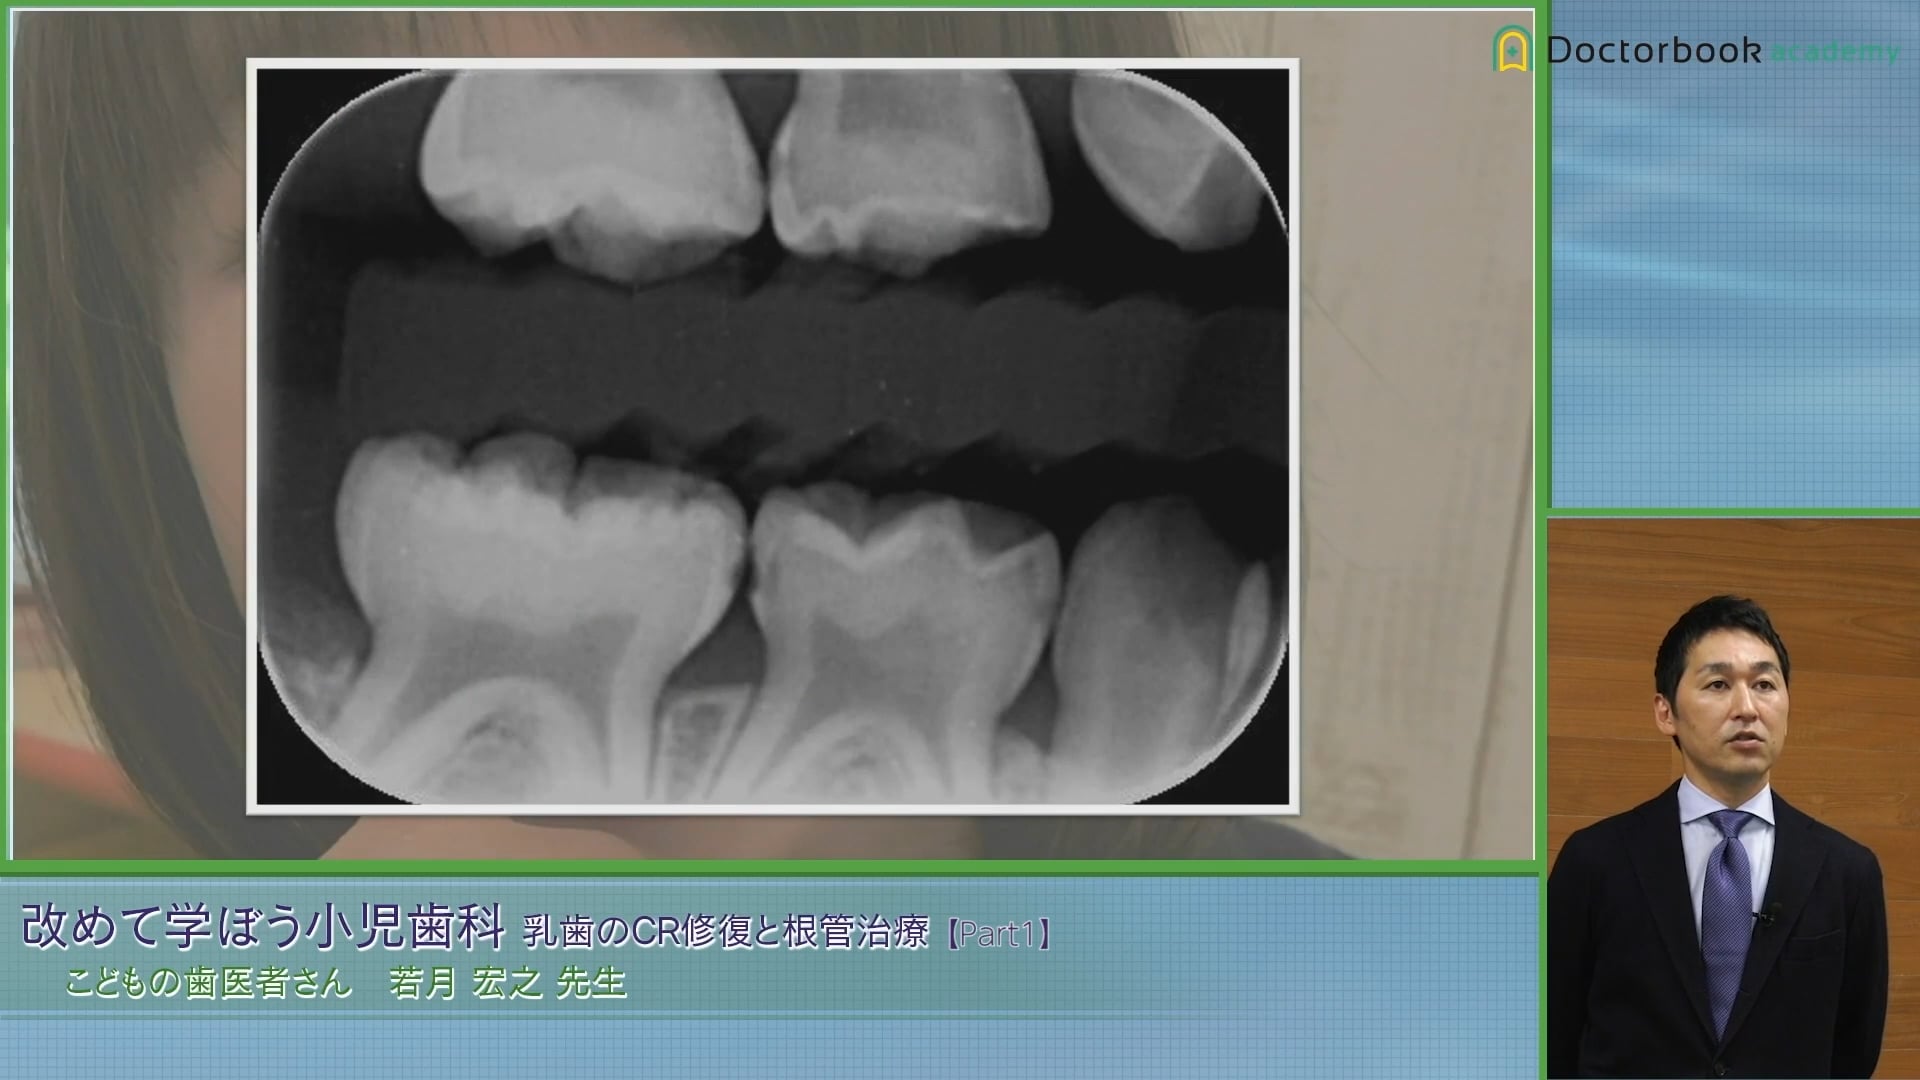

隣接面う蝕はバイトウィング

隣接面カリエスは見た目やノンワックスのフロスでも分からないことが多いです。隣接面カリエスを発見するためのレントゲンについて解説されています。